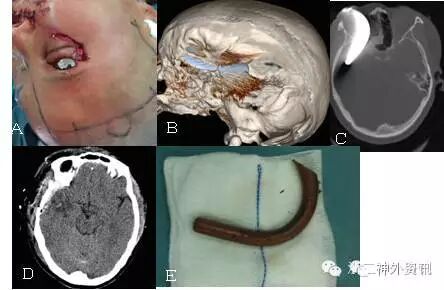

图8. 折叠刀刺入颅内,成功拔除(患者,男,37岁,A、B术前CT,C术后CT复查)。

图9. 钢棒入颅,成功拔除(患者,男,55岁,A、B术前CT,C术后CT复查)。

图10. 钢钩扎入眶颅,顺利拔除(患者,女,35岁,A、B、C术前,D术后CT复查,E取出钢钩)。

图11. 钢钎经口咽入颅,成功拔除(有点类似于本病例,患者,男,44岁)。

图12. 刀片插入眶颅,顺利拔除(患者,女,67岁)。

图13. 拔除枯竹(患者,女,61岁,详见浙二神外周刊(八))。

浙医二院作为“百年老店”,一直在创伤救治方面走在国内前列,是浙江省神经创伤、急诊医学等的中心,每年都有大量颅脑创伤等病人送来救治,其中不乏颅脑贯通伤病例。以下为近年来我们所救治的另外几例颅脑贯通伤病例,基本上都得到了满意的治疗效果。